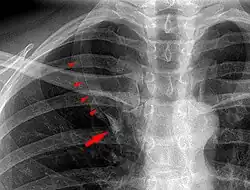

De lobus venae azygos als anatomische variant van een normale long wordt meestal als toevalsbevinding ontdekt bij radiologisch onderzoek. Op longfoto's is de fissura venae azygos namelijk als een gebogen witte lijn zichtbaar in het mediale bovenveld van de rechterlong.[1]